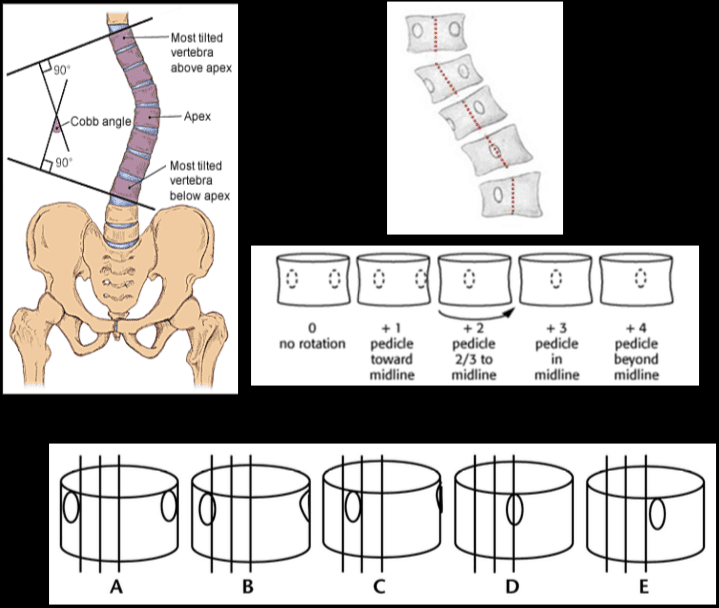

Studji dwar l-Immaġini

L-immaġini f'mard deġenerattiv tad-diska tintuża prinċipalment biex tiddeskrivi relazzjonijiet anatomiċi u karatteristiċi morfoloġiċi tad-diski affettwati, li għandha valur terapewtiku kbir fit-teħid ta 'deċiżjonijiet futuri għal għażliet ta' trattament. Kwalunkwe metodu ta 'immaġini, bħal radjografija sempliċi, CT, jew MRI, jista' jipprovdi informazzjoni utli. Madankollu, kawża sottostanti tista 'tinstab biss fi 15% tal-pazjenti billi l-ebda bidliet radjoloġiċi ċari ma huma viżibbli f'mard deġenerattiv tad-diska fin-nuqqas ta' ħernja tad-diska u defiċit newroloġiku. Barra minn hekk, m'hemm l-ebda korrelazzjoni bejn il-bidliet anatomiċi li dehru fuq l-immaġini u s-severità tas-sintomi, għalkemm hemm korrelazzjonijiet bejn in-numru ta 'osteofiti u s-severità ta' uġigħ fid-dahar. Bidliet deġenerattivi fir-radjografija jistgħu jidhru wkoll f'nies bla sintomi li jwasslu għal diffikultà biex jikkonformaw ir-rilevanza klinika u meta tibda l-kura. ("Marda tad-Diska Deġenerattiva" Fiżjopedja)

Ir-Radjografija

Din ir-radjografija ċervikali sempliċi rħisa u disponibbli b'mod wiesa 'tista' tagħti informazzjoni importanti dwar id-deformitajiet, l-allinjament, u bidliet deġenerattivi taż-żaqq. Sabiex tiġi ddeterminata l-preżenza ta 'instabilità ta' l-ispina u bilanċ sagittali, għandhom isiru studji ta 'flessjoni dinamika jew estensjoni.